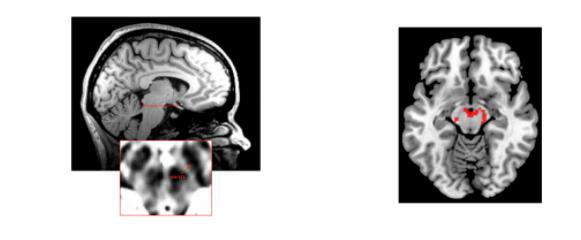

托莫娃和萨克斯使用功能核磁共振成像对禁食和隔离后的参与者进行扫描,揭示了他们的大脑对食物和社交互动的反应。右边的扫描图显示了中脑与奖励相关的活动

与戴琦和马修斯不同,托莫娃无法追踪单个神经元,但她可以在扫描的更大区域内追踪血液流动的变化,这种区域被称为体素(voxel);每个体素都显示了数千个神经元离散群体的活动变化。托莫娃重点研究了中脑的一些区域,这些区域富含与产生和处理神经递质多巴胺有关的神经元。

在其他实验中,这些区域已经与“想要”或“渴望”某种东西的感觉联系了起来。当一个人在饥饿的时候看到食物图片,或者当瘾君子看到与毒品相关的图像时,这些区域就会十分活跃。那么,如果给孤独者观看微笑的图片,他们的这些区域也会这样吗?

答案显而易见:在社交孤立之后,当受试者看到社交暗示的图片时,其大脑扫描结果显示,他们的中脑变得十分活跃。当受试者感到饥饿,但没有被社会孤立时,他们对食物暗示表现出类似的强烈反应,对社交暗示则没有反应。